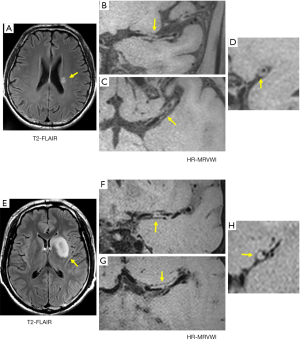

For the SSI group, no eccentric or concentric wall thickening was found in 5 of the 43 patients (11.6%). In the LSI group, all patients had eccentric or non-eccentric wall thickening of the MCA on the ipsilateral side of the cerebral infarction. A comparison of the number of quadrants with plaque formation and location of plaque distribution between the SSI group and LSI group is given in Tables 2 and 3, respectively. For the SSI group, the plaque in 13 patients involved only one quadrant, and the proportion was significantly higher than in the LSI group (34.2 vs. 7.1%, P=0.006). Figure 1 shows representative HR-MRVWI images of two patients with SSI and LSI, respectively. The plaque in both patients involved only one quadrant.

Furthermore, the 13 plaques were more frequently located in the superior (46.2%) and dorsal (38.5%) sides of the vessel wall. The occurrence of plaques involving two or more quadrants was approximately the same in the two groups, and plaques involving two quadrants were the most common distribution pattern in both groups: 17 and 19 plaques in SSI and LSI groups, respectively (Table 2). The plaque distribution in four quadrants was similar between the two groups. The ventral side was a relatively commonly involved quadrant, whereas the dorsal side was a relatively rarely involved quadrant.